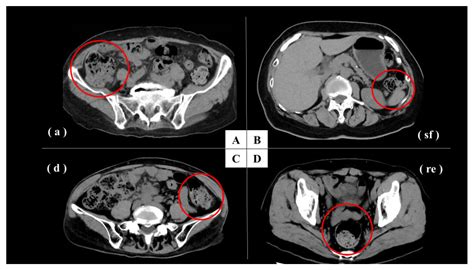

Understanding the internal health of your digestive system is crucial, and one term you might encounter during a clinical imaging report is a Moderate Stool Burden. This diagnosis, often provided after an X-ray or CT scan, indicates that there is a noticeable accumulation of fecal matter within the colon. While the term sounds clinical and perhaps concerning, it is a common finding in medical imaging that helps healthcare providers assess bowel habits and digestive functionality. Essentially, it suggests that your colon is holding more waste than what is considered optimal for standard transit, which can be a key indicator for issues such as chronic constipation or sluggish motility.

When a radiologist identifies a Moderate Stool Burden, they are observing the density and distribution of feces within the large intestine. Unlike a severe impaction—which represents a medical emergency where the bowel is completely blocked—a moderate burden is often interpreted as a “backed-up” state. It means that the waste is moving through the digestive tract slower than it should, but it has not reached a point of complete obstruction.

This finding is often subjective, based on the radiologist’s interpretation of the scan. It serves as a diagnostic tool rather than a final disease diagnosis. It prompts doctors to look closer at your medical history, current symptoms, and lifestyle factors to determine if an underlying condition is preventing regular evacuation.